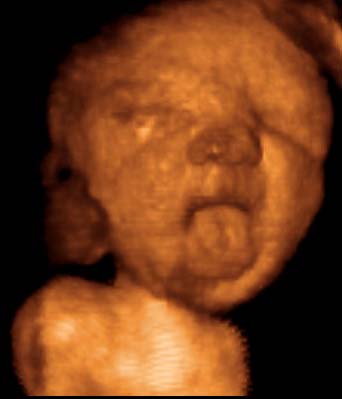

4D-ULTRAHANG

Fotógaléria / Arcok

A képeket Györfi Mátyás készítette.

36. hét